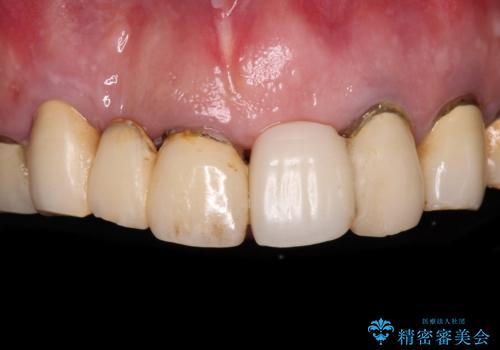

転倒で折れてしまった前歯 インプラントによるオールセラミックブリッジ治療

- 転倒により前歯3本が折れてしまったとのことで、インプラントによる治療を希望して来院された患者様です。

既に近医で真ん中の歯1本は抜歯されており、その隣の2本も破折していると言われたとのことでした。

診断をした結果、前医の診断の通り、2本とも破折しており、既に抜去している歯を含めて3本の抜歯が必要な状態でした。

抜歯する歯の両隣も治療が必要と思える歯であったため、広範囲なオールセラミックブリッジによる治療も提案しましたが、患者様本人の希望もあってインプラント2本による欠損部のみのブリッジ治療を行うこととしました。